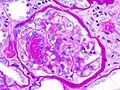

![]() Микрофотография узелкового гломерулосклероза при синдроме Киммельстил-Уилсона. | |

Диабети́ческая нефропа́тия (от др.-греч. διαβαίνω, — «перехожу, пересекаю», др.-греч. νεφρός — «почка» и др.-греч. πάθος — «страдание, болезнь») (нефропатия при сахарном диабете, синдром Киммельстила-Уилсона, диабетический гломерулосклероз) — термин, объединяющий весь комплекс поражений артерий, артериол, клубочков и канальцев почек, возникающих в результате нарушения метаболизма углеводов и липидов в тканях почки. Распространённость диабетической нефропатии достигает 75% лиц с сахарным диабетом, чаще других наблюдается следующая патология почек[2]:

Синдром Киммельстил-Уилсона (диабетический гломерулосклероз) — узелковая форма гломерулосклероза, специфическая для сахарного диабета, получила название в честь патологоанатомов Киммельстил и Уилсона, обнаруживших и описавших в 1936 году своеобразное узелковое склеротическое поражение клубочков почек у лиц с сахарным диабетом. При диабете наблюдаются диффузный и узелковый варианты поражения почечных клубочков. Узелковая форма, описанная Киммельстил и Уилсоном, чаще встречается при сахарном диабете 1-го типа уже вскоре после манифестации заболевания, постепенно прогрессирует, приводя в итоге к диабетическому гломерулосклерозу и развитию ХПН. В клинической практике термином «синдром Киммелльстил-Уилсона» характеризуют нефросклеротическую, азотемическую стадию поражения почек при сахарном диабете. Последнее время этим термином пользуются реже, пользуясь диагнозом «Диабетическая нефропатия, хроническая болезнь почек 5 стадии» (Ефимов А. С. и соавт.)[3].